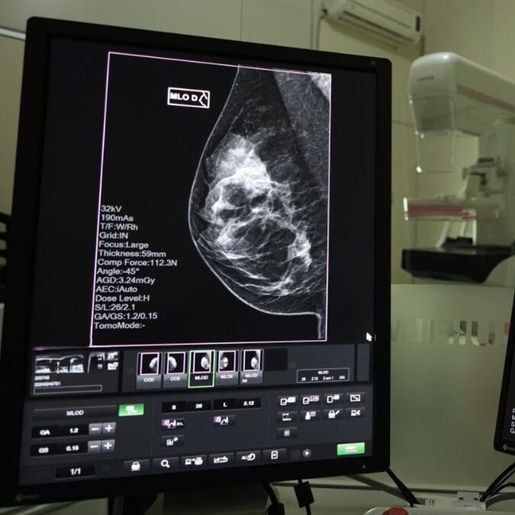

A detecção precoce do câncer de mama é fundamental para aumentar as chances de tratamentos menos invasivos e com maiores taxas de sucesso. As mamografias são realizadas pelo SUS, via Atenção Primária à Saúde, com prestadores dos municípios e Consórcios de Saúde.

Hospitais de gestão estadual, que prestam serviços de saúde da mulher e possuem mamógrafos, também realizam os exames.

O SUS garante acesso gratuito a medicamentos, exames, internações e procedimentos necessários. Ao identificar um nódulo ou qualquer outro sintoma suspeito, a recomendação é procurar uma Unidade Básica de Saúde (UBS) para atendimento. De lá, segundo a Secretaria de Saúde, o paciente é encaminhado para realização de exames, entre eles a mamografia, ultrassonografia e ressonância magnética.